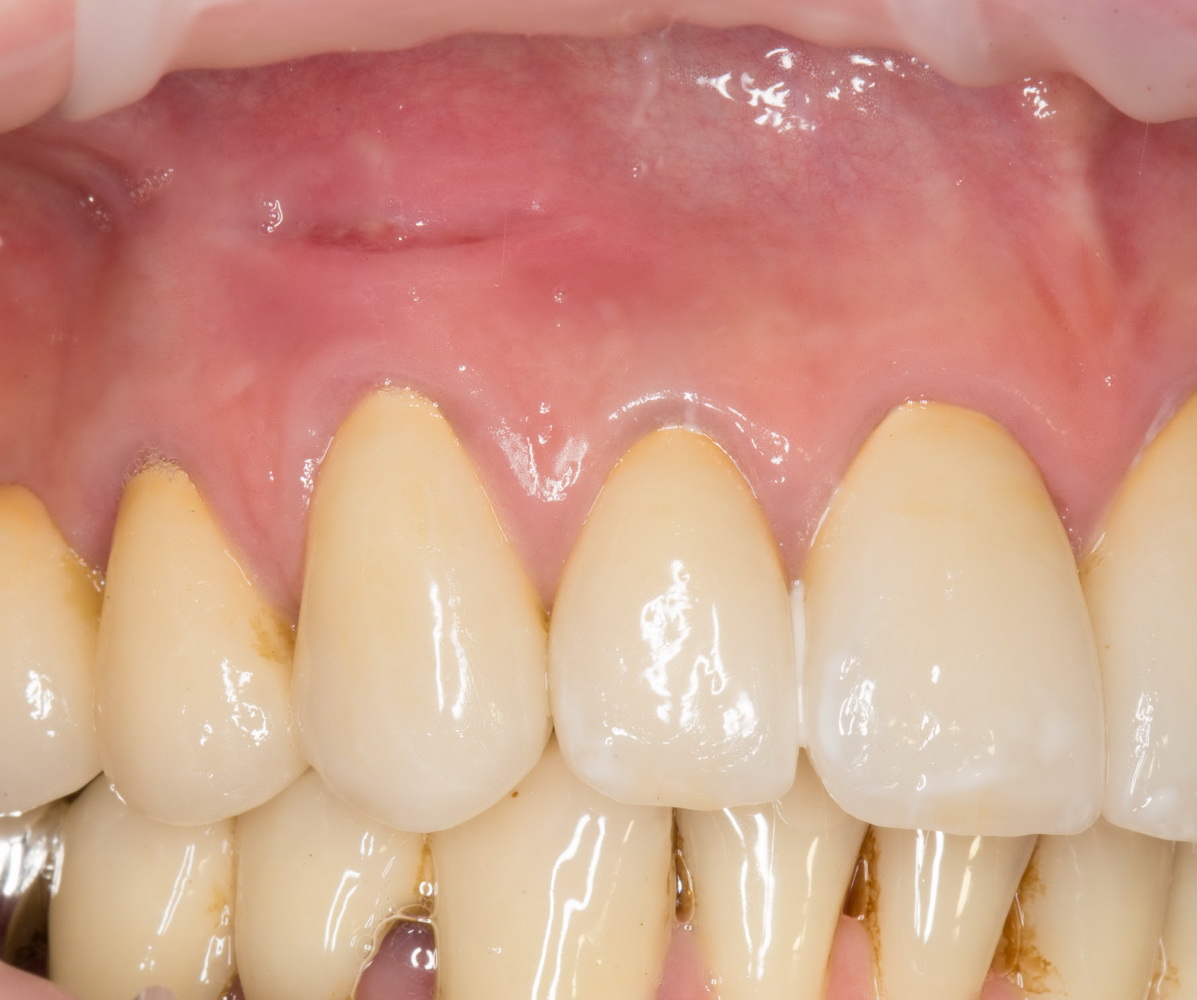

Итак, прошло, примерно, 6 месяцев после имплантации. На имплант клыка установлена постоянная металлокерамическая коронка. Вот она:

Или вот — так любят демонстрировать свои работы врачи-ортопеды:

Есть разница? Сейчас этот зуб выглядит лучше, чем окружающие.

По-моему, очень круто получилось. Давиду респект. Пациентке тоже.